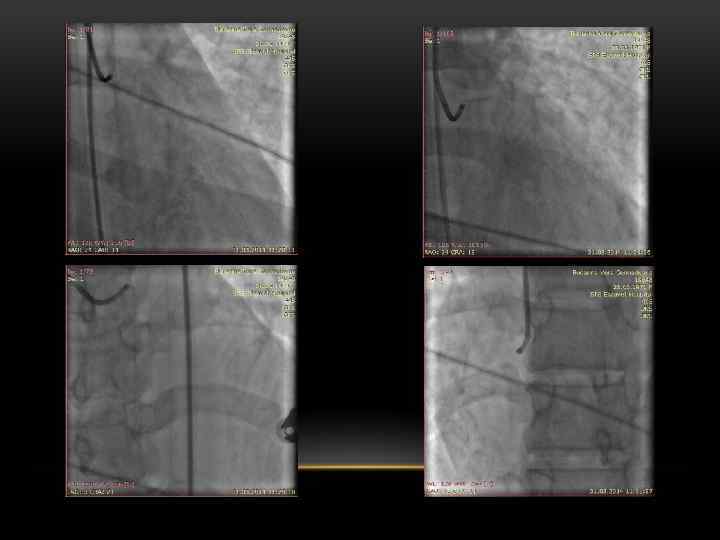

ЧРЕСКОЖНАЯ ТРАНСЛЮМИНАЛЬНАЯ КОРОНАРНАЯ АНГИОПЛАСТИКА Первую в мире коронарную ангиопластику выполнил в 1977 году Andreas Roland Gruentzig (1939 -1985). Он назвал это хирургическое вмешательство чрескожной чреспросветной коронарной баллонной ангиопластикой.

АНГИОПЛАСТИКА ПРИ ОСТРЫХ КОРОНАРНЫХ СИНДРОМАХ • Первичная ( «прямая» ): проводится больному без предварительной тромболитической терапии. • Вторичная: ранняя (спасительная) - выполняется в остром периоде ИМ с целью восстановления коронарного кровотока при неэффективности тромболизиса, при наличии кардиогенного шока у больных моложе 75 лет, при СН Killip III, желудочковых аритмиях; отсроченная - выполняется после купирования острых явлений ишемии миокарда у больных высокого риска по данным неинвазивных тестов и у больных с постинфарктной стенокардией.

АБСОЛЮТНЫЕ ПОКАЗАНИЯ К ПЕРВИЧНОЙ АНГИОПЛАСТИКЕ • Должна быть выполнена в инфаркт зависимой артерии в течении первых 12 часов после приступа. • Пациенты моложе 75 лет, перенесшие кардиогенный шок в течение 36 часов после инфаркта, которые подходят для реваскуляризации и которая может быть выполнена в течение 18 часов после шока. • Пациенты с кардиогенным шоком или отеком легких в течение первых 12 часов после приступа и в течение 90 минут после поступления.

АБСОЛЮТНЫЕ УСЛОВИЯ ДЛЯ ПРОВЕДЕНИЯ АНГИОПЛАСТИКИ ПРИ ОКС • Должна выполняться опытным хирургом, выполняющим более 75 процедур в год в коллективе, выполняющем более 200 плановых процедур в год. • Если от начала приступа прошло менее 3 часов и есть возможность выполнить первичную ангиопластику в течение часа. • При выполнении ангиопластики кардиохирургическое отделение должно быть готово для выполнения неотложного коронарного шунтирования! • Если таких условий нет, предпочтительна тромболитическая терапия.